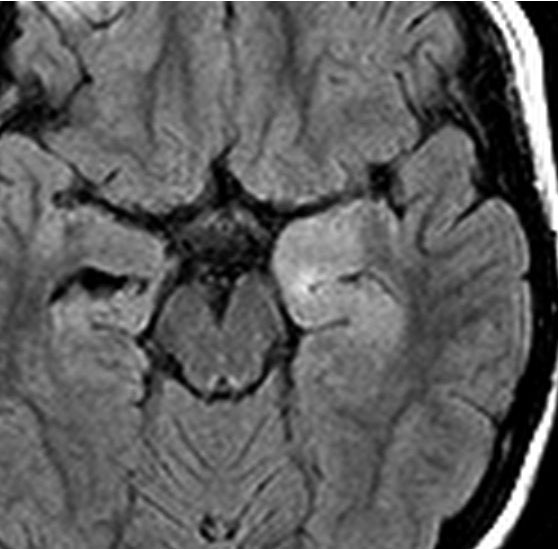

10才の時に,複雑部分発作(症候性てんかん)で発症しました。吐き気を感じた後に嘔吐して意識が遠くなる(意識減損)という症状であり,側頭葉てんかんです。脳波では左側頭葉に徐波律動がみられました。発作は頻回でしたがカルバマゼピンの投与で抑制されていましたが,MRIで腫瘍が発見されました。

左内側側頭葉グリオーマ mesial temporal glioma と呼ばれる腫瘍です。左の扁桃体,海馬鉤,海馬,海馬傍回に腫瘍が浸潤しています。T2強調画像とFLAIRでまだらな高信号で境界ははっきりしません。mass effectが少なく,増殖増大傾向のある腫瘍には見えないのが特徴です。下段右のように部分的にガドリニウム増強されるのも神経節細胞腫の特徴かもしれません。しかし,神経節膠腫,乏突起膠腫,乏突起星細胞腫(グレード2)なども疑われます。

手術中の脳波モニターでは,棘波が上側頭回の後方(ウェルニッケ領域)に存在し,深部電極刺入で海馬近傍にも棘波がみられましたが,もちろん上側頭回や海馬の切除はしませんでした。扁桃体 amygdala と海馬鈎 uncus の腫瘍部分のみを切除して手術を終了しています。海馬と海馬傍回には腫瘍を残しました。上のMRIは,その後6年経過した後のものですが腫瘍は全く同じ大きさです。抗てんかん薬も止めて,発作は全く生じていません。このような腫瘍は,扁桃体と海馬鉤を摘出することで,発作を完全に止めることができることがあります。ですから,最初の手術では,リスクのある余分な脳切除をしません。